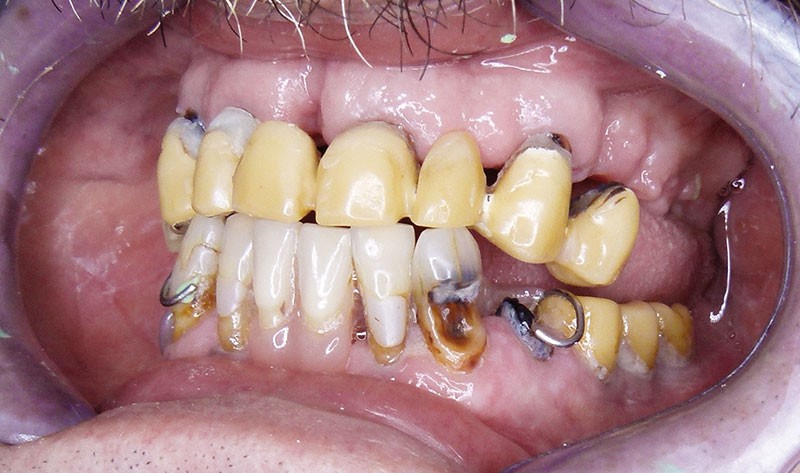

Monsieur L… se présente en décembre 2012 pour une demande de réhabilitation complète de sa cavité buccale. Il est âgé de 65 ans. Il présente un bon état de santé générale, sans pathologie restrictive. En revanche, son état bucco-dentaire est pour le moins problématique … Il est porteur de prothèses provisoires qui se sont délitées avec le temps. Plusieurs implants ont été mis en place auparavant, à la mandibule. Les restaurations d’usage n’avaient jamais été réalisées … (fig. 1 et 2).